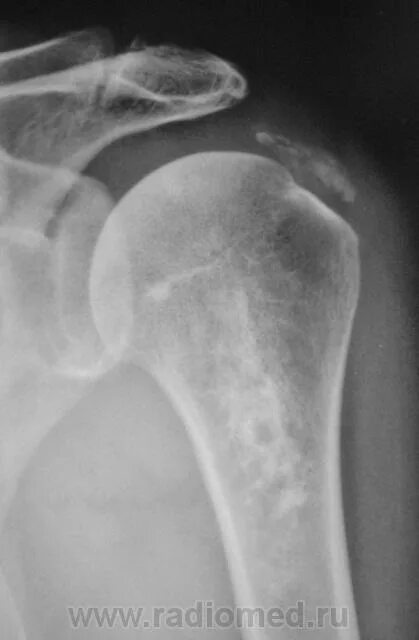

Обызвествление места прикрепления сухожилий